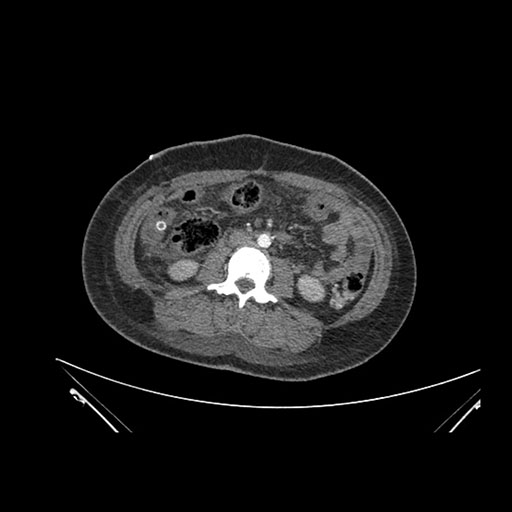

Axial Arterial

Imaging analysis

Based on initial findings, which issue(s) would you be most concerned about?